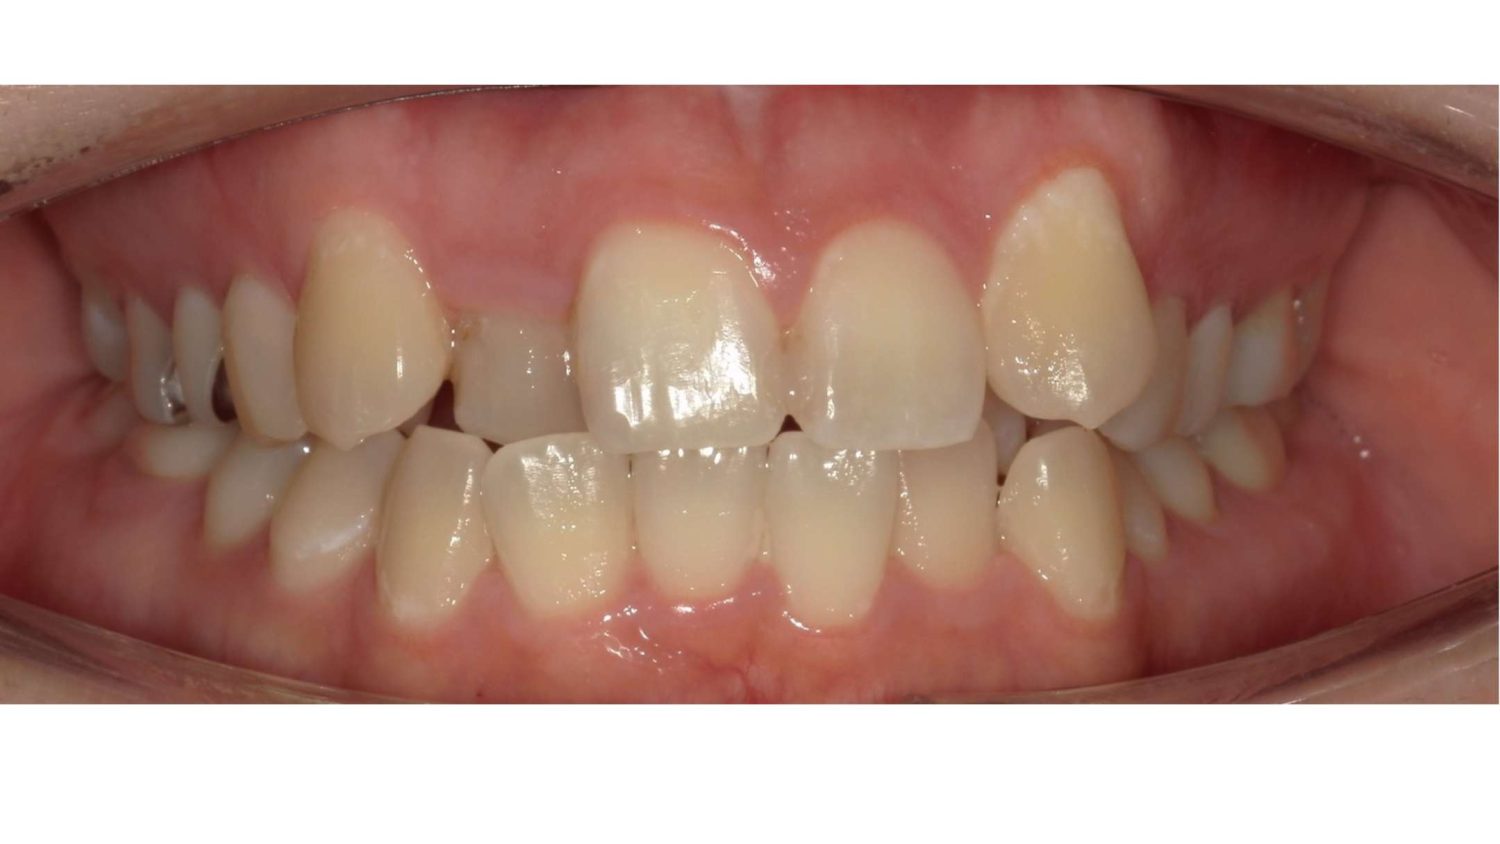

前歯だけの矯正の症例紹介②

Before

After

主訴

上の前歯の横の歯が後ろに引っ込んでいるのでセラミックの被せ物で治したい。

治療内容

ワイヤー矯正で治しました。

治療費

115,500円(税込)(リテーナー込み)

治療期間

4か月

通院回数

5回

想定されたリスク

※当該部位の上下のかみ合わせが反対になっていましたので、上の歯を前に動かすときに引っかかって動かない可能性がありました。

セラミックの被せ物で治すと健全な歯を削ることになってしまうので、患者様と相談し、矯正治療で治すことにしました。